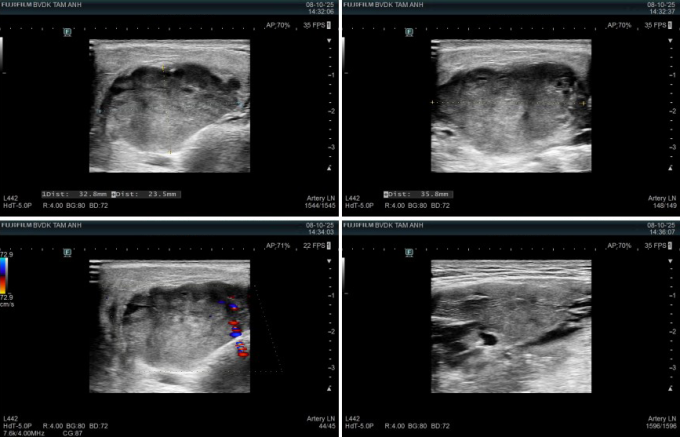

Kết quả chụp chiếu vùng mang tai và cổ cho thấy u tuyến mang tai trái kích thước 29x15 mm, ranh giới rõ, bờ cong đều, không vôi hóa. Các tuyến nước bọt khác và hạch vùng cổ bình thường, chưa ghi nhận dấu hiệu viêm hay di căn. Bác sĩ còn phát hiện một vài nhân nhỏ ở tuyến giáp hai bên, kích thước lớn nhất 22x13 mm, lành tính.